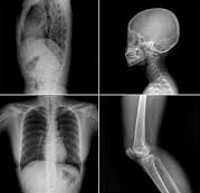

Рентгеновский. Метод лучевой диагностики с фиксацией изображения исследуемого участка. В классическом варианте предусмотрено использование изображений (рентгенограмм). В настоящее время, наряду с обычными рентгенограммами, цифровые носители могут использоваться для исправления изображения. Рентгенография позволяет получать информацию практически о любых участках человеческого тела. В большинстве случаев данные получаются благодаря естественному контрастированию различных органов и структур (при рентгенографии костей, суставов и легких или рентгенографии органов брюшной полости). Иногда искусственное контрастирование проводят для изучения определенной зоны (например, с помощью ирригоскопии или урографии).

Принимая во внимание область исследования, имеется контрастная рентгенограмма костей и суставов конечностей (разделенных на сегменты), прицельная и рентгенологическая рентгенография таза, позвоночника, черепа, грудной клетки и рентгенография органов абс. Существует также много видов контрастной рентгенографии: ирригация (исследование толстой кишки), холецистография (исследование желчного пузыря), урография (исследование почек и мочевыводящих путей), фистулография (исследование свищевых путей при остеомиелите) и.